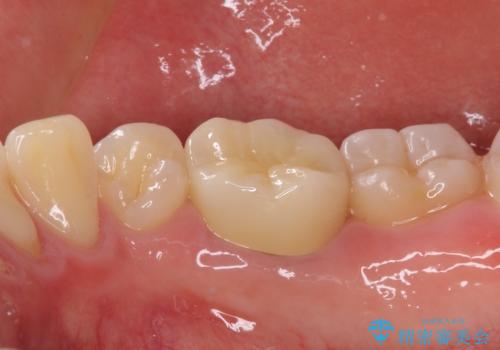

虫歯除去後に痛みは収まり、神経も保存することができました。

変色していた歯もセラミッククラウンで自然な色合いとなり、患者様には大変満足していただきました。